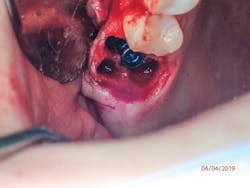

Therefore, if a patient has 5 mm of available bone height from the sinus floor, a maximum of 5 mm is prudent to expect from an indirect lift; therefore, an 8 mm to 10 mm implant is the ideal choice. The tapered iHex or MorsTorq implant provides safety when dealing with sinus areas, for three reasons. First, the taper helps prevent overinsertion toward the sinus cavity. Second, the abutment and transfer attached to the implant allows for more control. Finally, the rounded apex helps reflect the sinus floor without creating damage (figures 1-6).